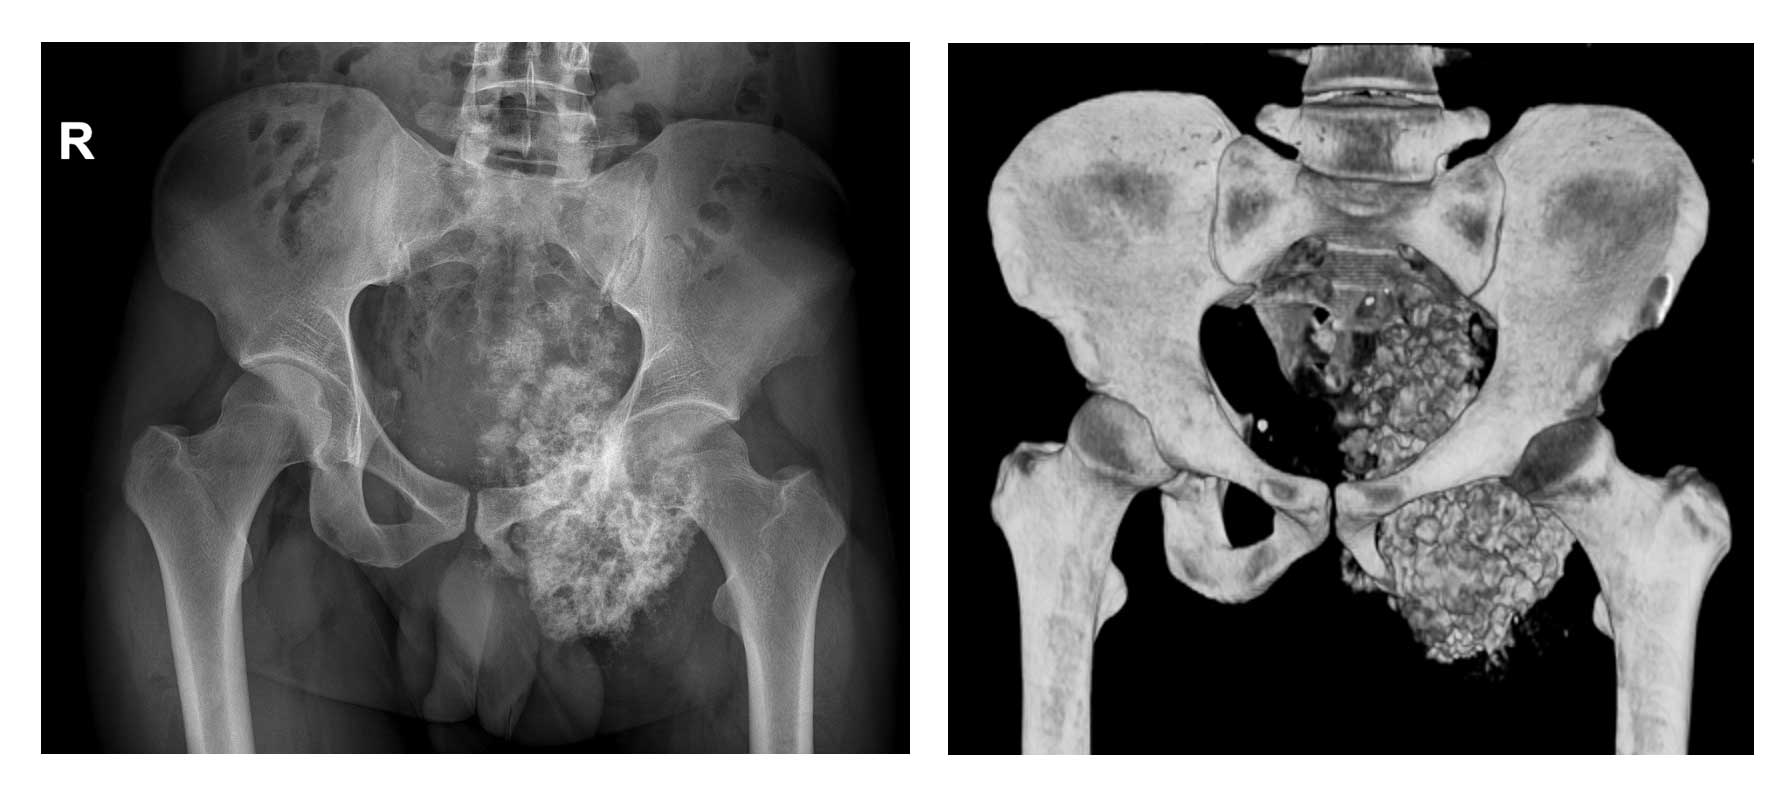

Ameliyat Öncesi: Röntgen ve 3BT’de sol asetabulum ve pubik kol kaynaklı obturator foromani ve hemipelvisi dolduran düzensiz sınırlı sklerotik tümör dokusu görülmekte.